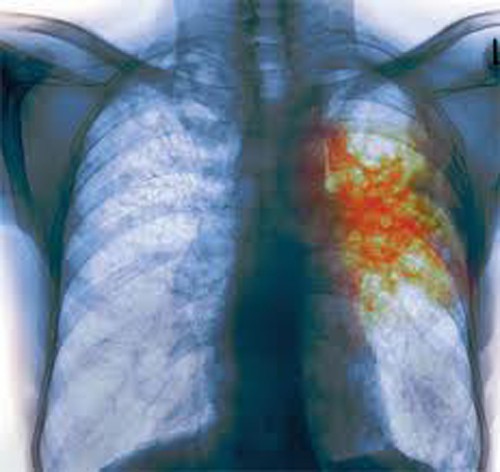

Рентген больного туберкулезом человекаПод туберкулезом специалисты понимают инфекционное заболевание, которое вызывается туберкулезными палочками (палочки Коха, микобактерии туберкулеза), сопровождается образованием гранулем в различных органах и развитием клеточной аллергии. Наиболее часто у больных выявляется туберкулез легких, суставов, костей, кожи и мочеполовых органов. Все эти формы туберкулеза требуют неотложного лечения, поскольку, в противном случае, заболевание прогрессирует и приводит к летальному исходу.